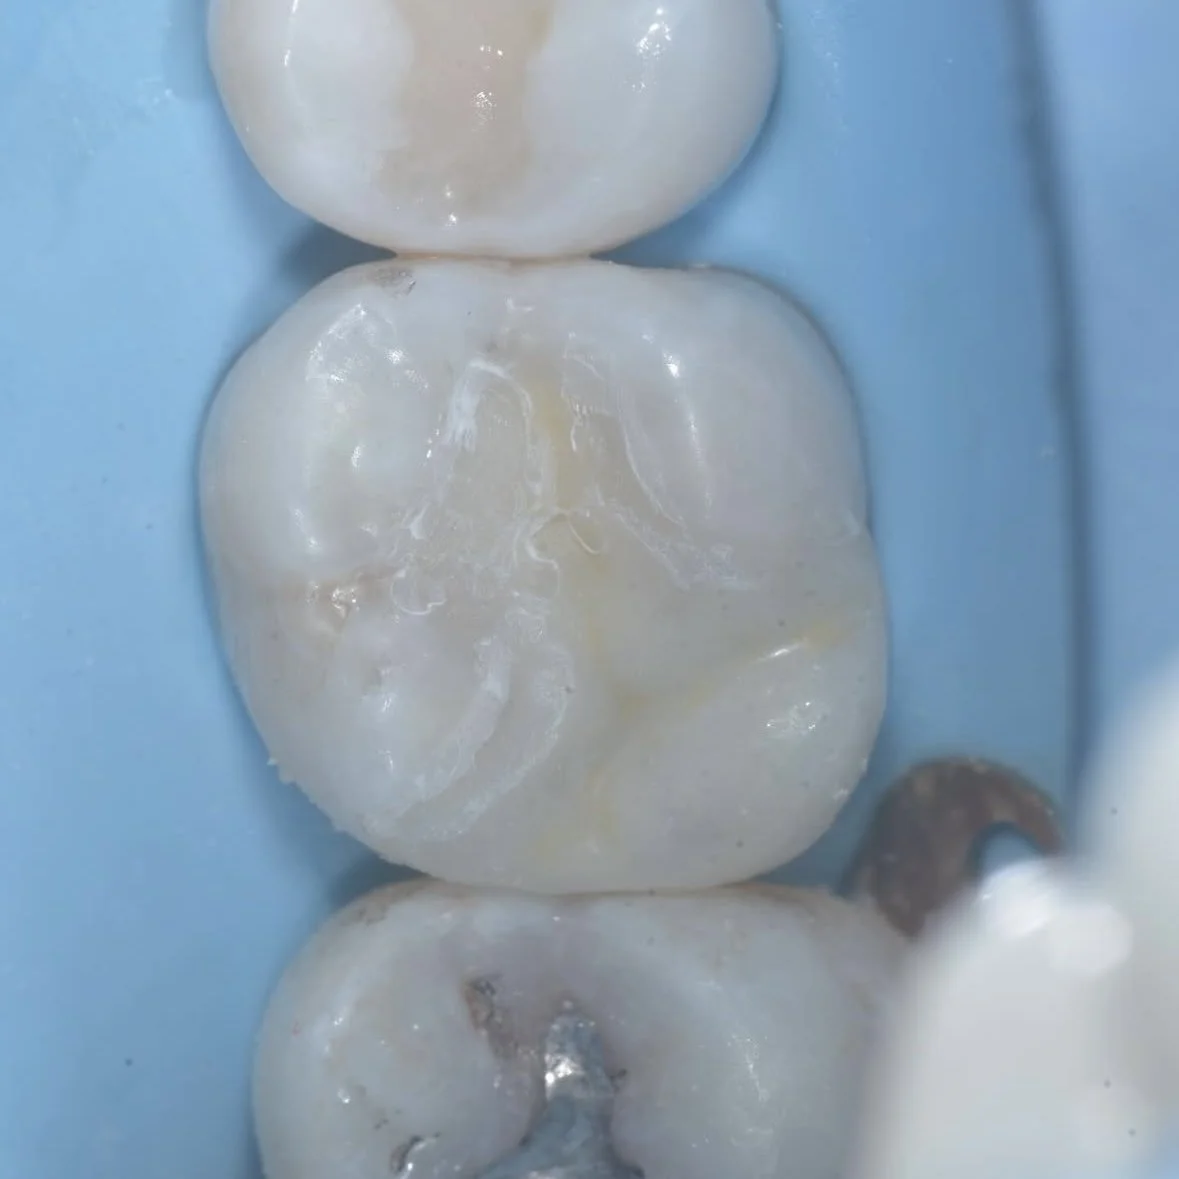

A poorly bonded composite restoration resulted in cuspal fracture as seen in the initial photo in this case by Dr. Davey Alleman, DMD.

Just because composite looks like a tooth, does not mean it functions like a tooth. This poorly bonded composite resulted in a cuspal fracture. Case by Dr. Davey Alleman, DMD.